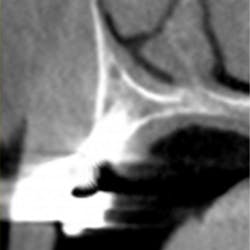

CBCT and MCT have been shown to be more sensitive than standard imaging at measuring bone mineral density, bone-to-implant contact, and maturity levels of bone around dental implants. (5) Different imaging systems have different conversion errors, and standardization of Hounsfield units and Grey values should not be made when comparing different scanners. (6) In other words, the image density around implants of scans taken by different systems may mean different things. (7) In addition, artifact and scatter around the dental implant may preclude an attempt at measuring implant stability (figure 2). The reverse torque test works by means of a specified reverse force placed upon the dental implant as a means of testing integration. This method is often invasive and can result in implant explantation if not carefully utilized. (8)